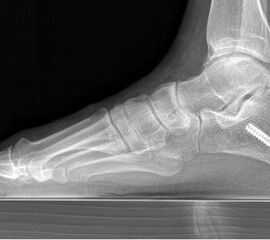

Abbildung Nr. 1: Röntgen Fuß: dp und seitlich stehend.

Es konnte, bei präoperativer Unfähigkeit zum einbeinigen Zehenspitzenstand, beim letzten Follow up in 62% der Fälle ein schmerzloser einbeiniger Zehenspitzenstand erreicht werden. Der Saltzmann-Winkel konnte von präoperativ 11° (7-17°) auf 3° (1-8°) korrigiert werden. Der seitliche Metatarsale I Winkel wurde von 18° präoperativ (13-23°) auf 7° (5-13°) postoperativ korrigiert. Der talonaviculare Überdeckungswinkel konnte von präoperativ 10° (4-18°) auf postoperativ 7° (2-15°) reduziert werden.